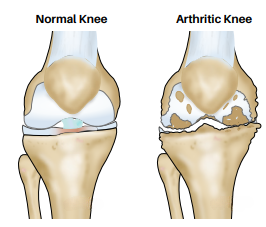

The knee joint is formed by Femur (thigh bone), tibia (leg bone) and patella Damage to the joint is called arthritis and is caused by Obesity, Meniscus tears, Malalignment (“bow-leg”) deformity overloading one compartment, instability (ligament tears) and rheumatological disorders.

Faulty knee alignment (bow-leg or knock-knee) overloads one compartment, resulting in cartilage injury, meniscus tears and joint space narrowing. As the joint space reduces, the alignment also worsens leading to a vicious cycle of joint destruction and deformity. Fortunately correction of the alignment at an early stage can restore knee function and postpone joint replacement